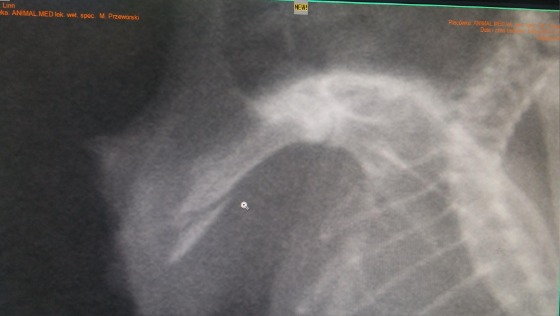

A oto zdjęcie RTG jej "łapki" tuż po zabiegu: